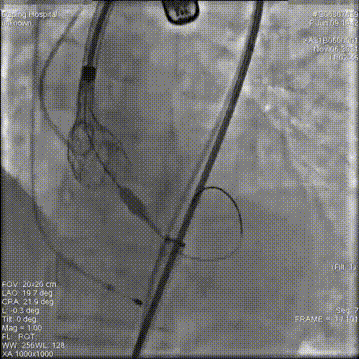

主动脉根部造影

18mm球囊预扩

第一次释放,位置过高回收定位

第二次释放,位置过低再回收释放

第三次瓣膜释放定位

23mm瓣膜释放中

20mm球囊后扩前造影

术后造影